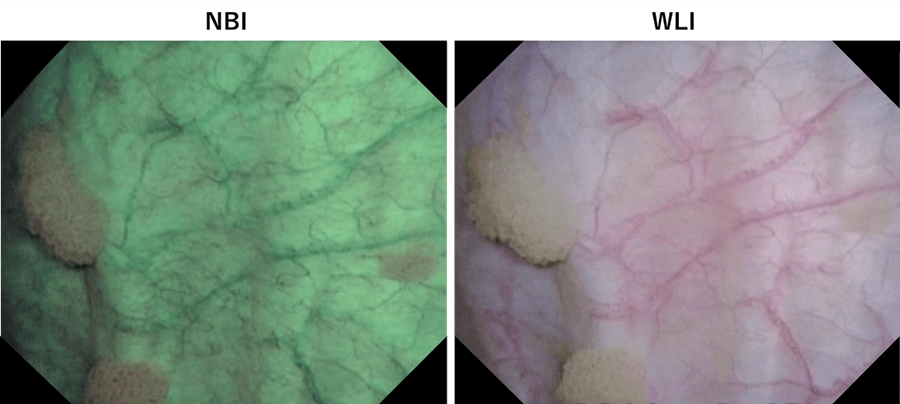

For TURBT, we mark the outside edge of the tumor before resection to identify the minimum area for resection. NBI helps determine the area for resection by clearly showing the tumor margins.

When viewing a tumor with associated lesions by WLI, lesions at the edge of tumor may be overlooked. After marking the tumor margins with WLI, switching to NBI sometimes allows us to find suspicious lesions outside the demarcated area. (Fig. 5, top). Therefore, we mark the area for resection under NBI observation before resection (Fig. 5, bottom).

Fig. 5. Top: White area observed with NBI is the margin marked under WLI observation. It is obvious that the papillary tumor extends outside the marked area. Bottom: Marking the edge of the tumor for the abnormal lesion identified with NBI. The area looks wider than the actual tumor when seen with WLI.